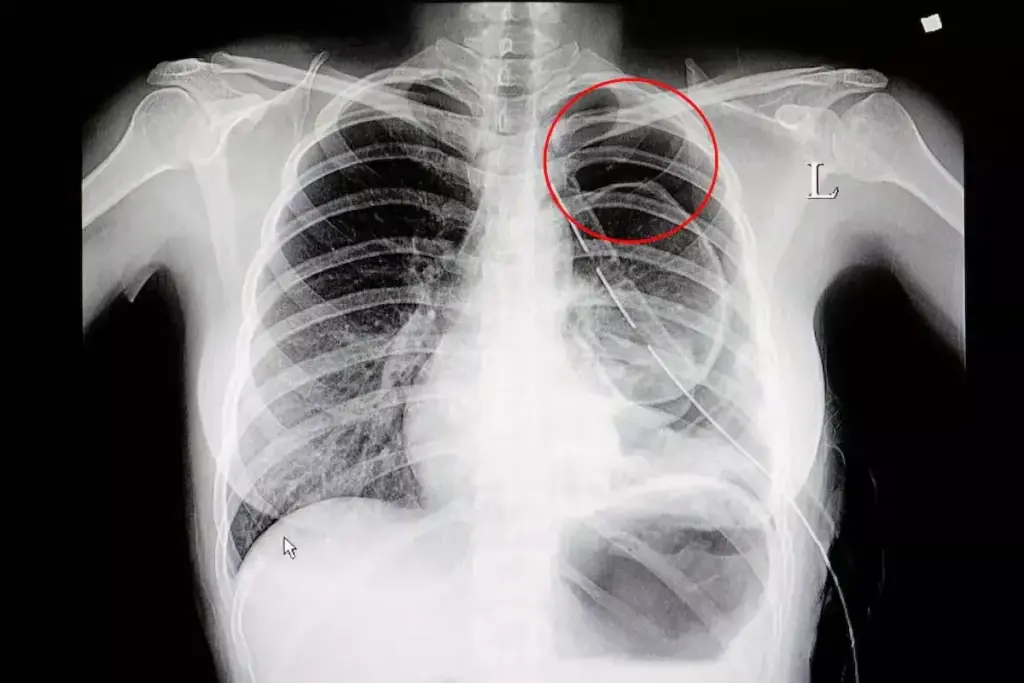

X-Ray Manifestations

X-rays are not as good as CT scans but can hint at bronchiectasis. On an X-ray, you might see:

- Ring shadows: These are dilated bronchi seen head-on.

- Tram-track opacities: These are parallel lines from thickened bronchial walls seen sideways.

These signs are not as clear as CT scans but can help confirm bronchiectasis. This is true when symptoms point to the disease.